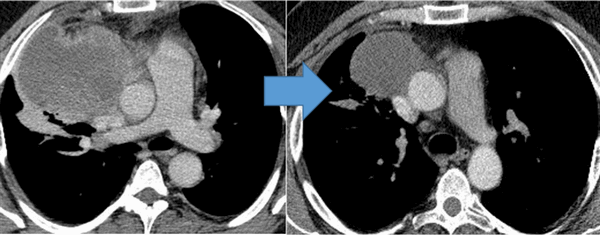

Показания к химиотерапии определяются степенью распространенности процесса, наличием легочных/внелегочных метастазов. Стандартным режимом химиотерапии при герминогенных опухолях является режим «BEP», включающий блеомицин, этопозид и цисплатин. Для пациентов с дыхательной недостаточностью, обширным поражением легких, во избежание легочной блеомициновой токсичности, как альтернативный вариант, может быть использованы режимы химиотерапии VIP (этопозид, ифосфамид, цисплатин) или ЕР (этопозид, цисплатин).

Для оценки эффективности химиотерапии каждые 2 цикла и после ее окончания проводится компьютерная томография исходных зон поражения, перед каждым циклом мониторинг уровня опухолевых маркеров. Рост маркеров на фоне лечения или после его завершения, а также замедление их снижения свидетельствует об активности опухолевого процесса и необходимости проведения второй линии химиотерапии.

![Метастазы в легких до лечения и после 4х циклов химиотерапии по схеме «ВЕР» (КТ грудной клетки)]()

Метастазы в легких до лечения и после 4х циклов химиотерапии по схеме «ВЕР» (КТ грудной клетки)

При проведении химиотерапии необходимо регулярно оценивать ее эффективность. Для этого каждые 2 цикла и после ее завершения проводится КТ тех областей, которые изначально были поражены опухолями. Также перед каждым циклом проверяется уровень онкомаркеров в крови. Если на фоне терапии или после ее окончания уровень онкомаркеров растет либо замедляется его снижение, то это говорит о том, что опухолевый процесс активен и нужно проводить вторую линию химиотерапии.